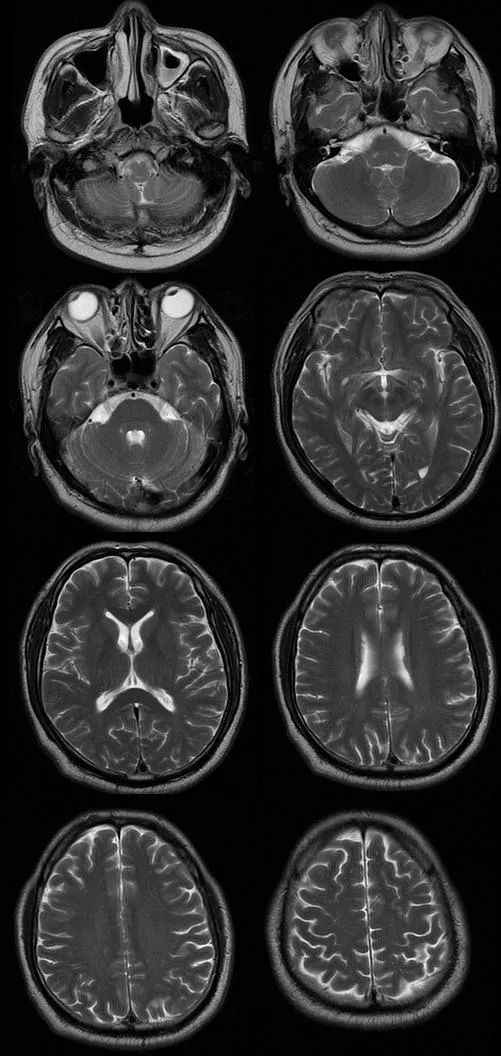

遗憾的是胸腰部 MRI 中 T1、T2、STIR 均未见明显异常,我们进一步完善头部 MRI,如下图:

T2

从影像学可以看出 T2FLAIR、T1、T2 似乎也未见明显异常,此时该如何诊断,定位到底在哪里呢?

让我们再仔细看一下 DWI:

DWI 提示右侧延髓背外侧小点状高信号,弥散受限,提示急性脑梗死。